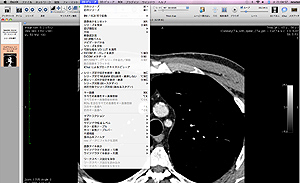

OsiriX(オザイリクス)は、医用画像ビューワの表示とその画像からの分析す

るために開発された高性能なDICOMビューワです。また同時に DICOM通信

OsiriX は臨床医みずからがプログラミングして開発されており、実際の医療現場で役立つシステムとして発展していると思われます。